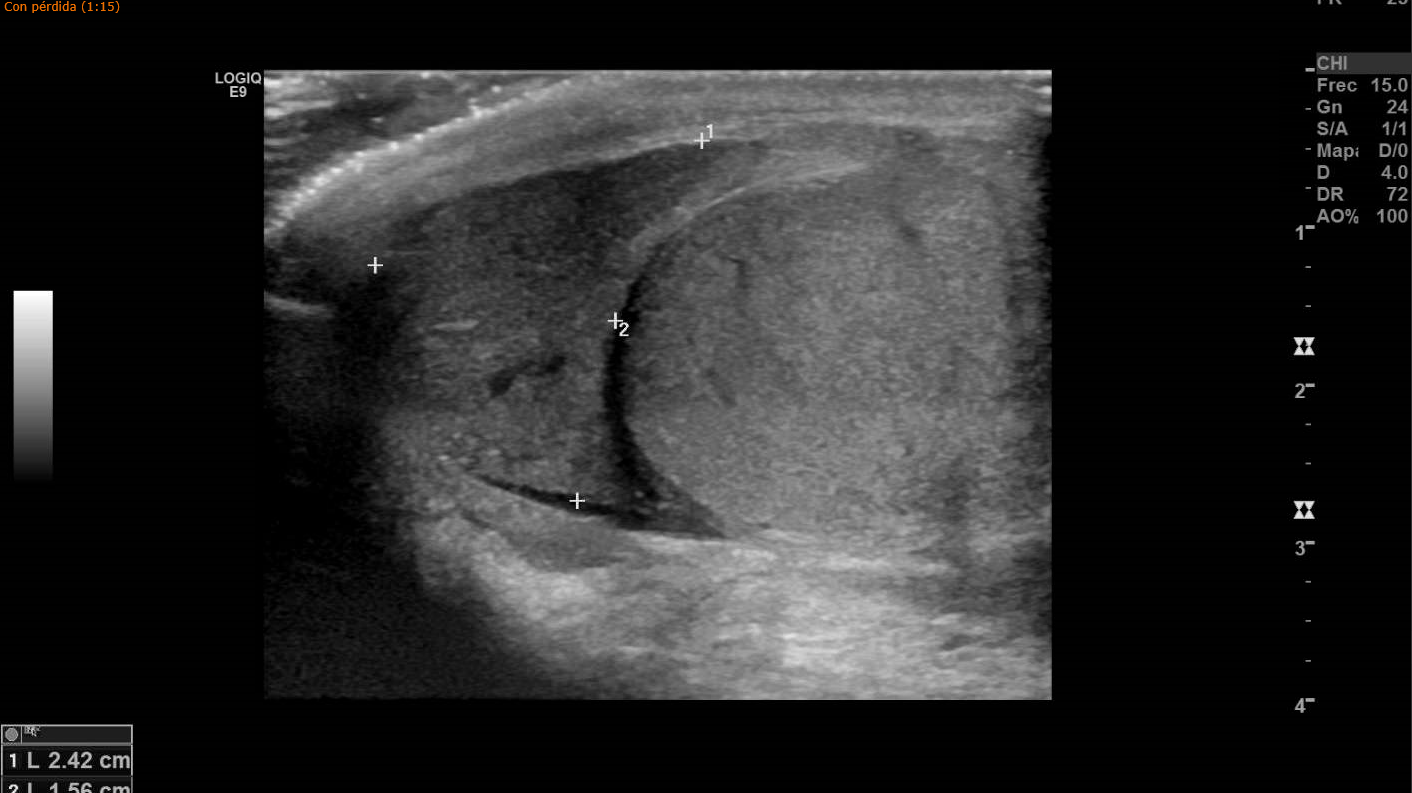

Para confirmar la sospecha se le realiza ecografía testicular, apreciando colección hemática en borde superior de bolsa escrotal izquierda, conservando flujo arterial y venoso. Impresiona de línea hipoecogénica que atraviesa el parénquima testicular, correspondiendo con rotura traumática de testículo izquierdo.